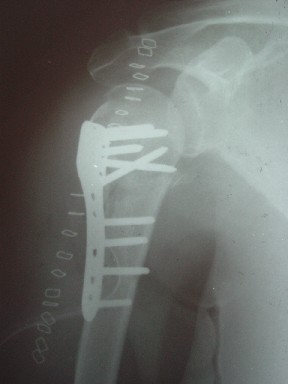

Уважаемые коллеги

сделать закрытую репозицию с помощью ЭОПа совсем не сложно, после этого еще проще провести 3-6 спиц и получить красивую рентгенограмму. Есть только небольшая проблема это ROTATOR CUFF. Для плечевого сустава только костное восстановление не достаточно. для функции плечевого сустава нужны вращатели.

Давайте представим себе состояние манжетки вращателей после вывиха плеча, а еще и с отрывным переломом бугров. Головка может и прирастет, еесли не будет аваскулярного некроза, но хорошего функционального результата не ждите.

Висеть будет красиво. У людей физически активного периода жизни нужно открыть, восстановить костную анатомию и восстановить сухожильный аппарат.

В этом плане Locking plate очень хороша так как позволяет начать движения сразу после операции.

Клинические снимки - 3 недели после операции

с уважением М. Беренштейн

Спасибо за участие в дискуссии -перелом шейки плеча, для себя я прояснил многие технические моменты...

Посылаю послеоперационные Рг граммы.